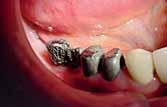

There was a missing 6 and 7 on each side with compromised 4 and 5 on each.

The volume of available bone was insufficient to place a root form implant on the site of 7 (C-h available bone) a ridge mapping technique was used and a (C-w available bone) was also encountered.

The use of short implant in this case was not a treatment of choice; the crown - implant ratio is > 1.

A unilateral subperiosteal implant was suggested.